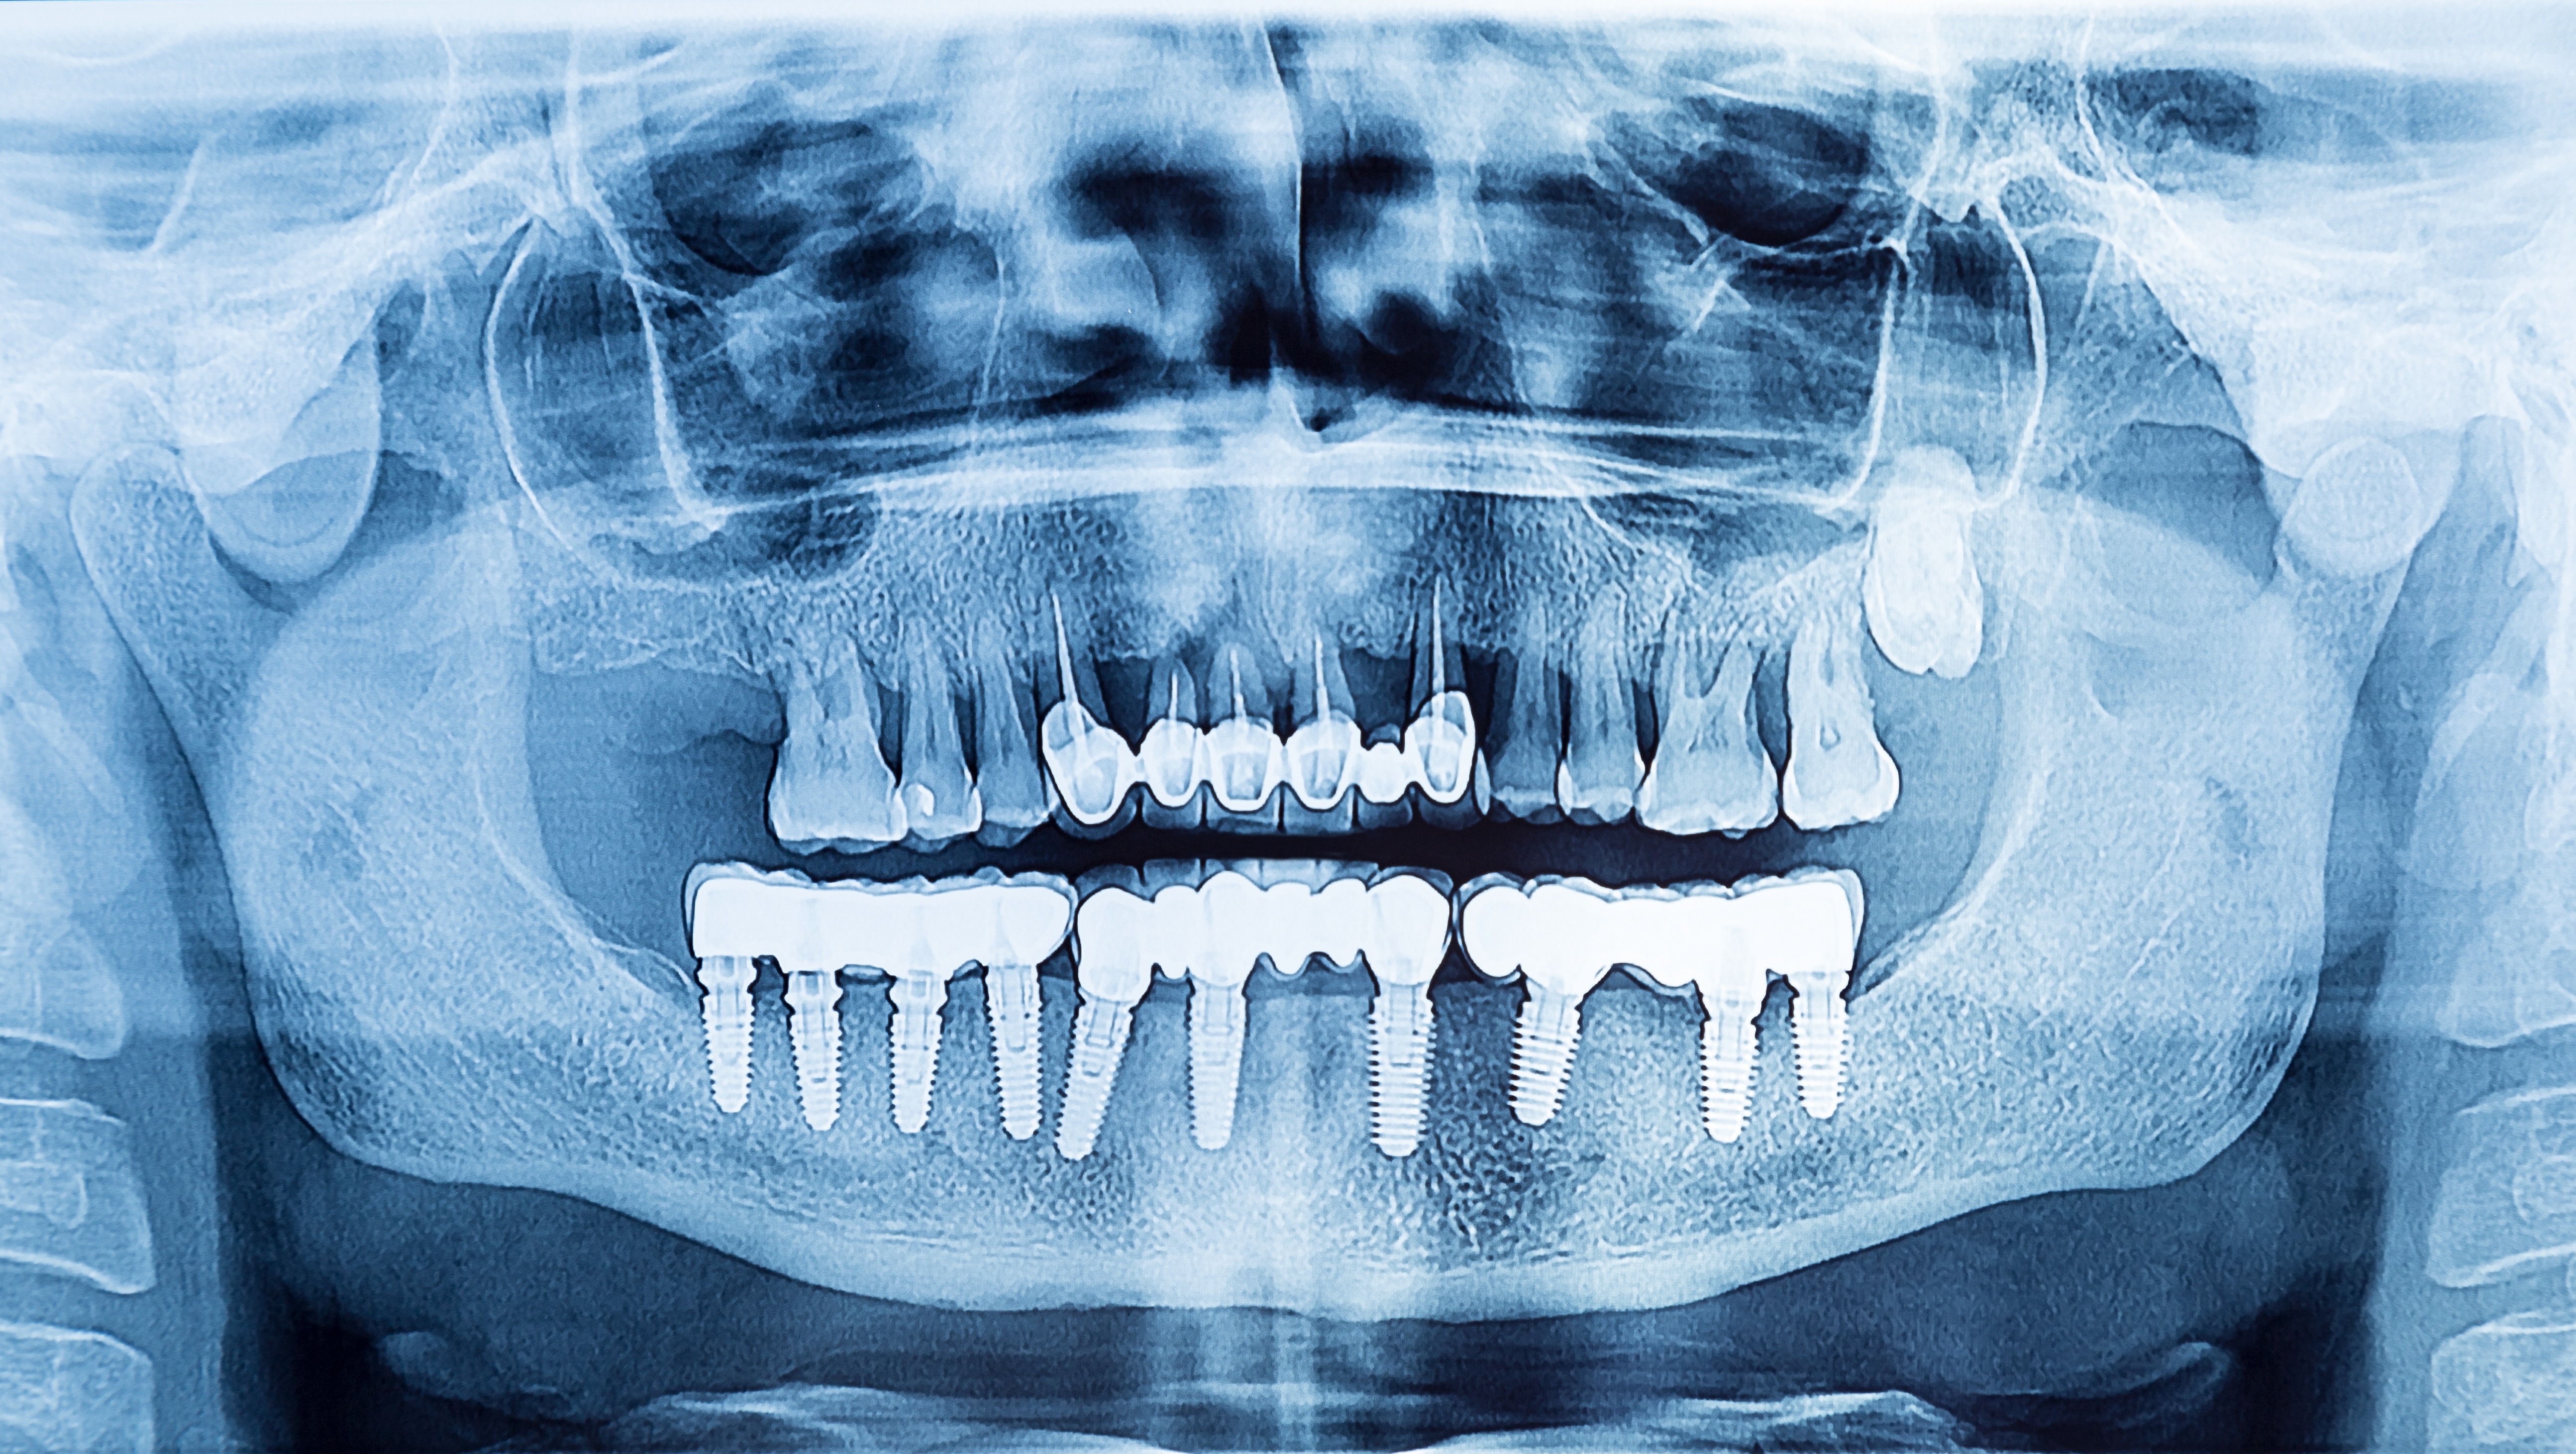

To be able to diagnose peri-implant diseases correctly, it is helpful to have good-quality, informative X-rays. However, periapical bitewing X-rays of implants in particular can often turn out blurry. There is, however, one very simple rule you can follow to correct these images and to depict implant threads clearly and precisely, thus enabling exact determination of the patient’s bone level. Furthermore, this rule is easy to remember and, above all, can be implemented rapidly in daily clinical practice:

What does this mean exactly? Regardless of whether you are taking an X-ray of an implant in the first/fourth or second/third quadrant, if the right side of the implant in the X-ray is blurred, then the beam must be raised. This means the beam must be ‘aimed’ higher, in order to image the right side of the implant more clearly. But if the left side of the implant in the X-ray is blurred, then the beam must be lowered. This means the beam should be ‘aimed’ lower, in order to image the left side of the implant more clearly.